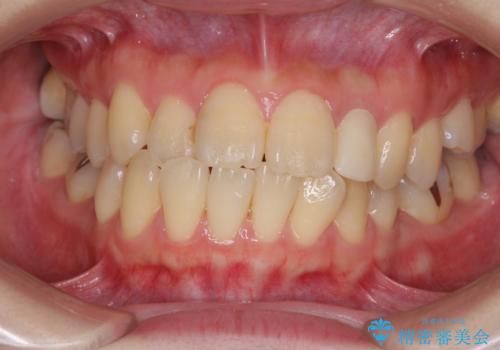

- 下顎の歯が舌側に倒れていることと、前歯の咬み合わせの不具合を気にして来院された患者様です。

受け口傾向の口元であるため、下顎左右小臼歯各1歯を抜歯して歯列を整えることとしました。

前歯には治療中の仮歯が装着されていたため、矯正治療後にオールセラミッククラウンにて補綴治療を行うこととしました。